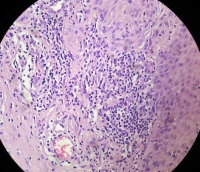

患者男,43岁,左眼结膜肿物生长半年。见左眼鼻侧结膜有一4×5mm蜡样新生物,质地中等,表面无破溃出血,色白,触之无出血。

送检暗红色碎组织一块,直径4mm。质地中等,灰白灰红色。

考虑符合:鳞状细胞乳头状瘤样变化

形态符合鳞状上皮乳头状瘤,伴慢性炎症。